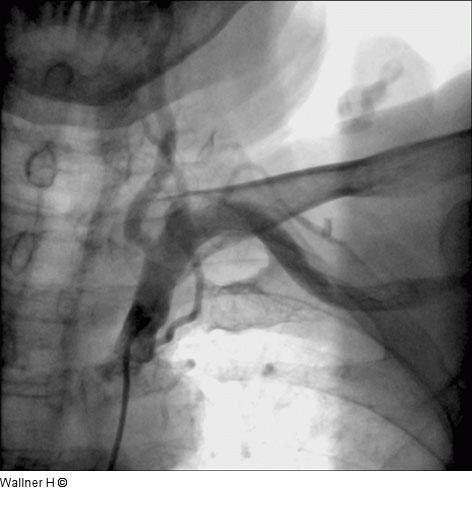

Abbildung 1: Judkins-Katheter Darstellung der linken Arteria subclavia mit normaler Weite und antegradem Fluß der Arteria vertebralis mittels Judkins-Katheter von transfemoral rechts. |

Darstellung der linken Arteria subclavia mit normaler Weite und antegradem Fluß der Arteria vertebralis mittels Judkins-Katheter von transfemoral rechts. |